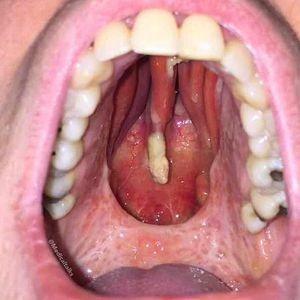

This man at his twenties presented to the surgical clinic with a hole in the roof of his mouth (palate) that allowed nasal regurgitation of food when he ate. The hole had been present for a year, and he requested surgical correction. The patient reported a 5-year history of nasal cocaine use from which he had recently abstained. Physical examination revealed a large perforation of the nasal septum and midline palate with and collapse of the nasal dorsum. Local complications of intranasal cocaine abuse include chronic rhinitis, sinusitis, epistaxis, ossification or necrosis of the nasal septum, and in rare cases, palatal perforation. The hole developed as a result of the use of cocaine, a potent vasoconstrictor (results in narrowing of blood vessels). The vasoconstrictive and caustic effect of the drug can produce direct irritation and ischemia of the nasal and palatine mucosa, leading over the long term to the creation of an oronasal perforation secondary to maxillary bone destruction. The destroyed anatomy was reconstructed by using standard surgical techniques.